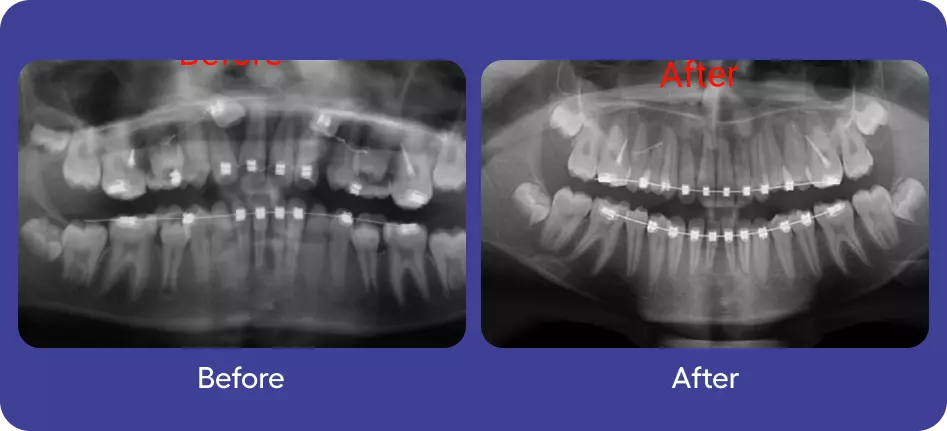

Surgical Orthodontics

Orthodontics

Full Mouth Rehabilitation